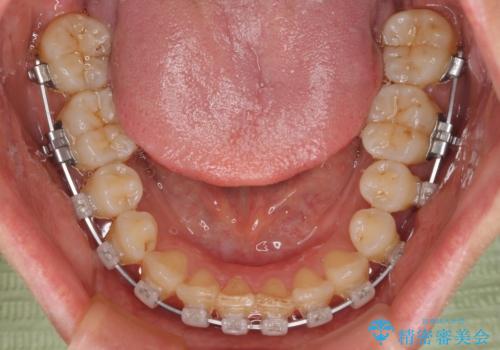

- クリアブラケット

- 治療期間

- 1年

仕事と小さいお子さんの育児に追われており、インビザラインの自己管理は続ける自信がないとのことで、ワイヤー装置による矯正治療を行うこととしました。